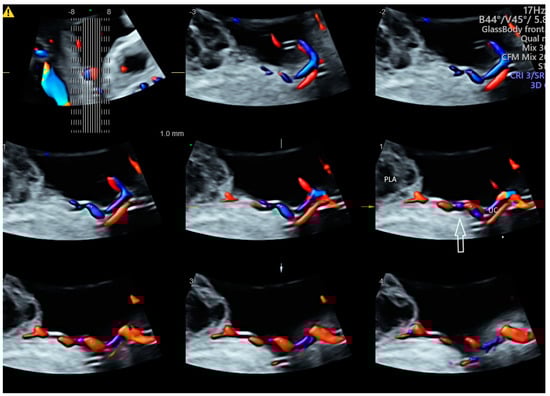

- Sun, W.; Chen, L.Z.; Yin, S.W.; Cai, A.L.; Yang, Z.Y. Non-invasive dynamic observation of placental vascular anastomoses in monochorionic twins: Assessment using three-dimensional sonography combined with tomographic ultrasound imaging. Placenta 2020, 95, 84–90. [Google Scholar] [CrossRef]

| Twin | Placental vascular anastomoses (HDFI) Intraplacental branches of umbilical artery (HDFI) | GBM TUI | Placental anastomoses in TTTS Different intraplacental vascularization in selective FGR TRAP, Cord entanglement in monoamniotic twin |